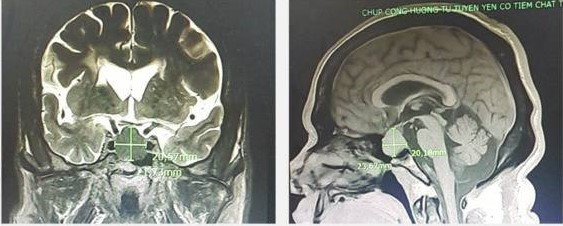

Kết quả từ chụp cộng hưởng từ 3.0 Tesla sọ não phát hiện 1 khối u tuyến yên (Marcroadenoma) kích thước 27x19x20mm và nhiều ổ nhồi máu não cũ nhân xám thần kinh trung ương 2 bên; các xét nghiệm cho thấy hoocmon tăng trưởng GH tăng (GH =234 ng/mL), hoocmon kích vỏ thượng thận ACTH tăng (ACTH = 84 pg/ mL).

| Hình ảnh khối u tuyến yên trên phim chụp cộng hưởng từ |